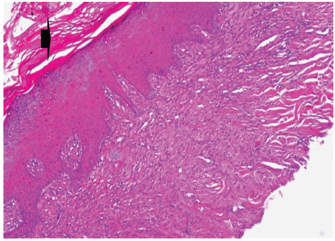

Histopathological findings of wound healing

At 7 days post wounding; the inflammatory reaction was moderate and characterized by polymorphonuclear cells and macrophages infiltration with the presence of small scab covering the wound surface. Early evidence of epithelization was detected and represented by the proliferation of epidermal epithelium under the scab. There was marked thickening and hyperplastic proliferation of epidermal epithelium at the free wound edge (Fig. 6). The dermal tissue underlying the wound area showed few polymorphonuclear cells infiltration and more abundant mononuclear cells. Fibroplasia and angiogenesis were detected in the dermis and more extensive in deeper areas of the dermis which characterized by fibroblast and angioblast proliferation forming immature young granulation tissue (Fig. 7). At 14 days post wounding, the wound area was covered by a complete layer of epidermal epithelium indicating a good epithelization rate of the wound. Proliferation of cutaneous appendages was detected. The newly formed epithelium was thick and showed partial keratinization and epithelial differentiated stratum containing polyhedral keratinocyte with the appearance of keratohyalin granules in their cytoplasm (Fig. 8). The dermal tissue showed deposition of parallel well organized and interconnected collagen bundles that arranged parallel to epidermis associated with enhanced angiogenesis represented by well-developed blood capillaries (Fig. 9). At 21 days post wounding, remodeling of the formed epithelium with relatively small scar formation and mild restoration of skin appendages. Keratinized and differentiated stratum comprising the covering epithelium and the newly formed skin appendages from the basal epidermal epithelium were detected (Fig. 10). The dermal tissue revealed well-formed organized tissue consisted of parallel compact and interconnected bundles of collagen with scant angiogenesis (Fig. 11). At 28 days post wounding, well-formed scar tissue covering highly cellular organized tissue was detected (Fig. 12). The dermal tissue revealed well-arranged compact collagen bundles containing scarce blood vessels (Fig. 13).

Fig. 10. Skin of a goat from electroacupuncture group at 21 days post wounding showing keratinized (arrow head) and differentiated stratum comprising the covering epithelium (*) and the newly formed skin appendages from the basal epidermal epithelium (HE ×200).

Fig. 11. Skin of a goat from electroacupuncture group at 21 days post wounding showing well-formed organized tissue consisted of parallel compact and interconnected bundles of collagen with scant angiogenesis (arrow head) (HE ×200).